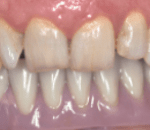

D] CHOICE OF PROSTHESIS

Fixed Prosthesis– might stimulate the bone but can be more difficult to adapt because of anatomical conditions and especially a reduced mouth opening. It also requires a high number of implants, which is not always possible in these patients.

It is recommended in case of short grafts13

The main problem with prosthesis remains the unfavourable implant–crown ratio and axis of the implants, which is not always the same as the axis of the prosthesis, leading to torque forces that may endanger implant survival.

The use of image-guided surgery and surgical guides decreases the risk and minimises the angulation between prosthetic axis and implant axis and also allows precise planning and accuracy of the rehabilitation15,16.

When placement of five implants or more is possible, a fixed ceramic prosthesis can be placed. A fixed hybrid ‘‘Branemark-like’’ prosthesis can be a good alternative for permanent rehabilitation. A bar framework